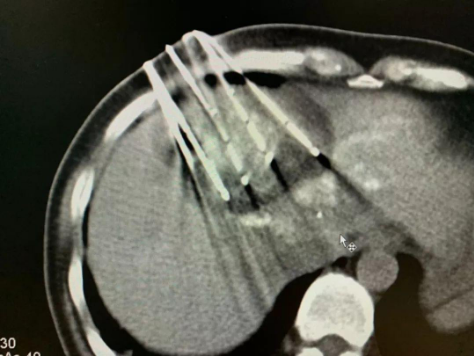

因为肝上的肿瘤比较大,血运很丰富,所以,复大的专家团队首先为她做了介入栓塞治疗。然后第二步,为她做了冷冻消融。接着,在椎体上的肿瘤做了冷冻加粒子植入。

做完治疗两周以后,再复查CT,肿瘤基本上都坏死了。作为一名影像学专家,苏女士自己看了片子以后,对自己的治疗效果非常满意。